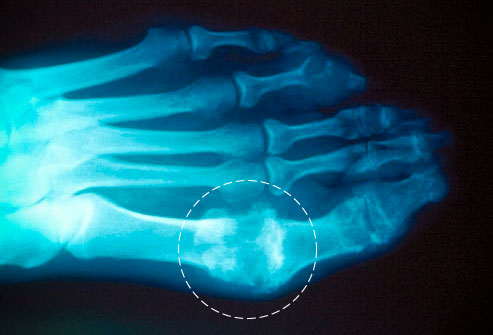

痛风的症状之大脚趾

大脚骨是痛风最易受累的地方。如果痛风没有完全治愈,疼痛常常反复发作。即使痛风的疼痛消失了,你也需要及时就医。因为i,随着时间的推移,痛风可以伤害关节、肌腱和其他组织。